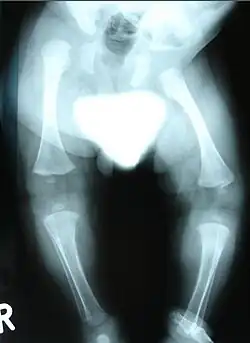

Obraz RTG kończyn dolnych dziecka z SWS, wyraźne cechy dysplazji kostnej